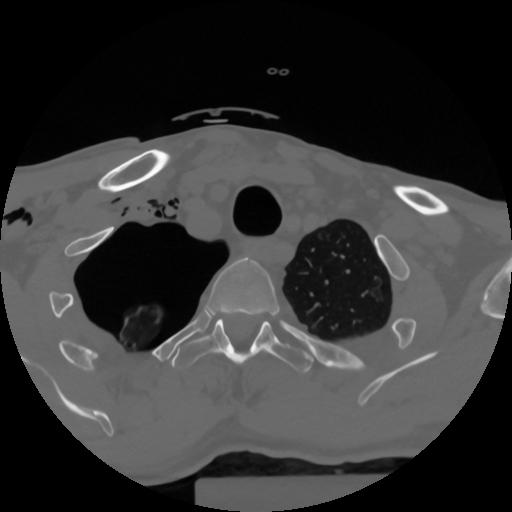

12 P.BLANDAS,,Vol,0.5,P.BLANDAS,,